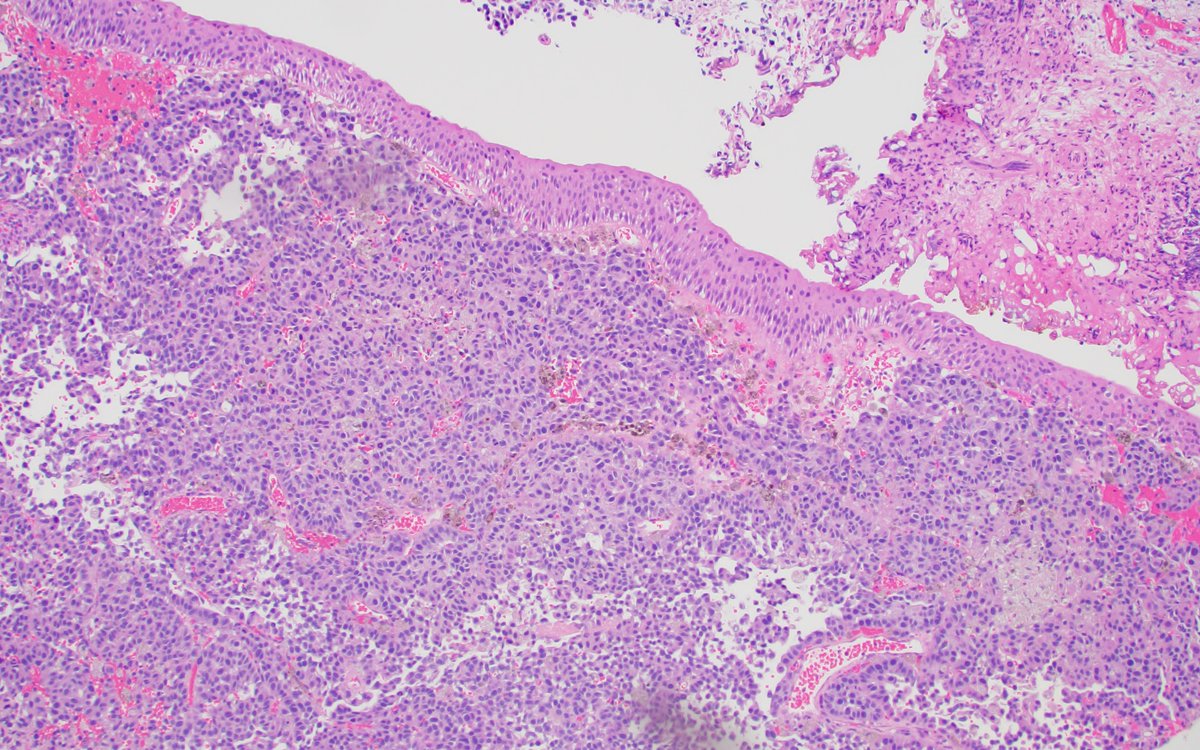

Collision of clear cell renal cell carcinoma and papillary renal cell carcinoma! This #prcc is trying to invade #ccrcc! #PathTwitter #gupath